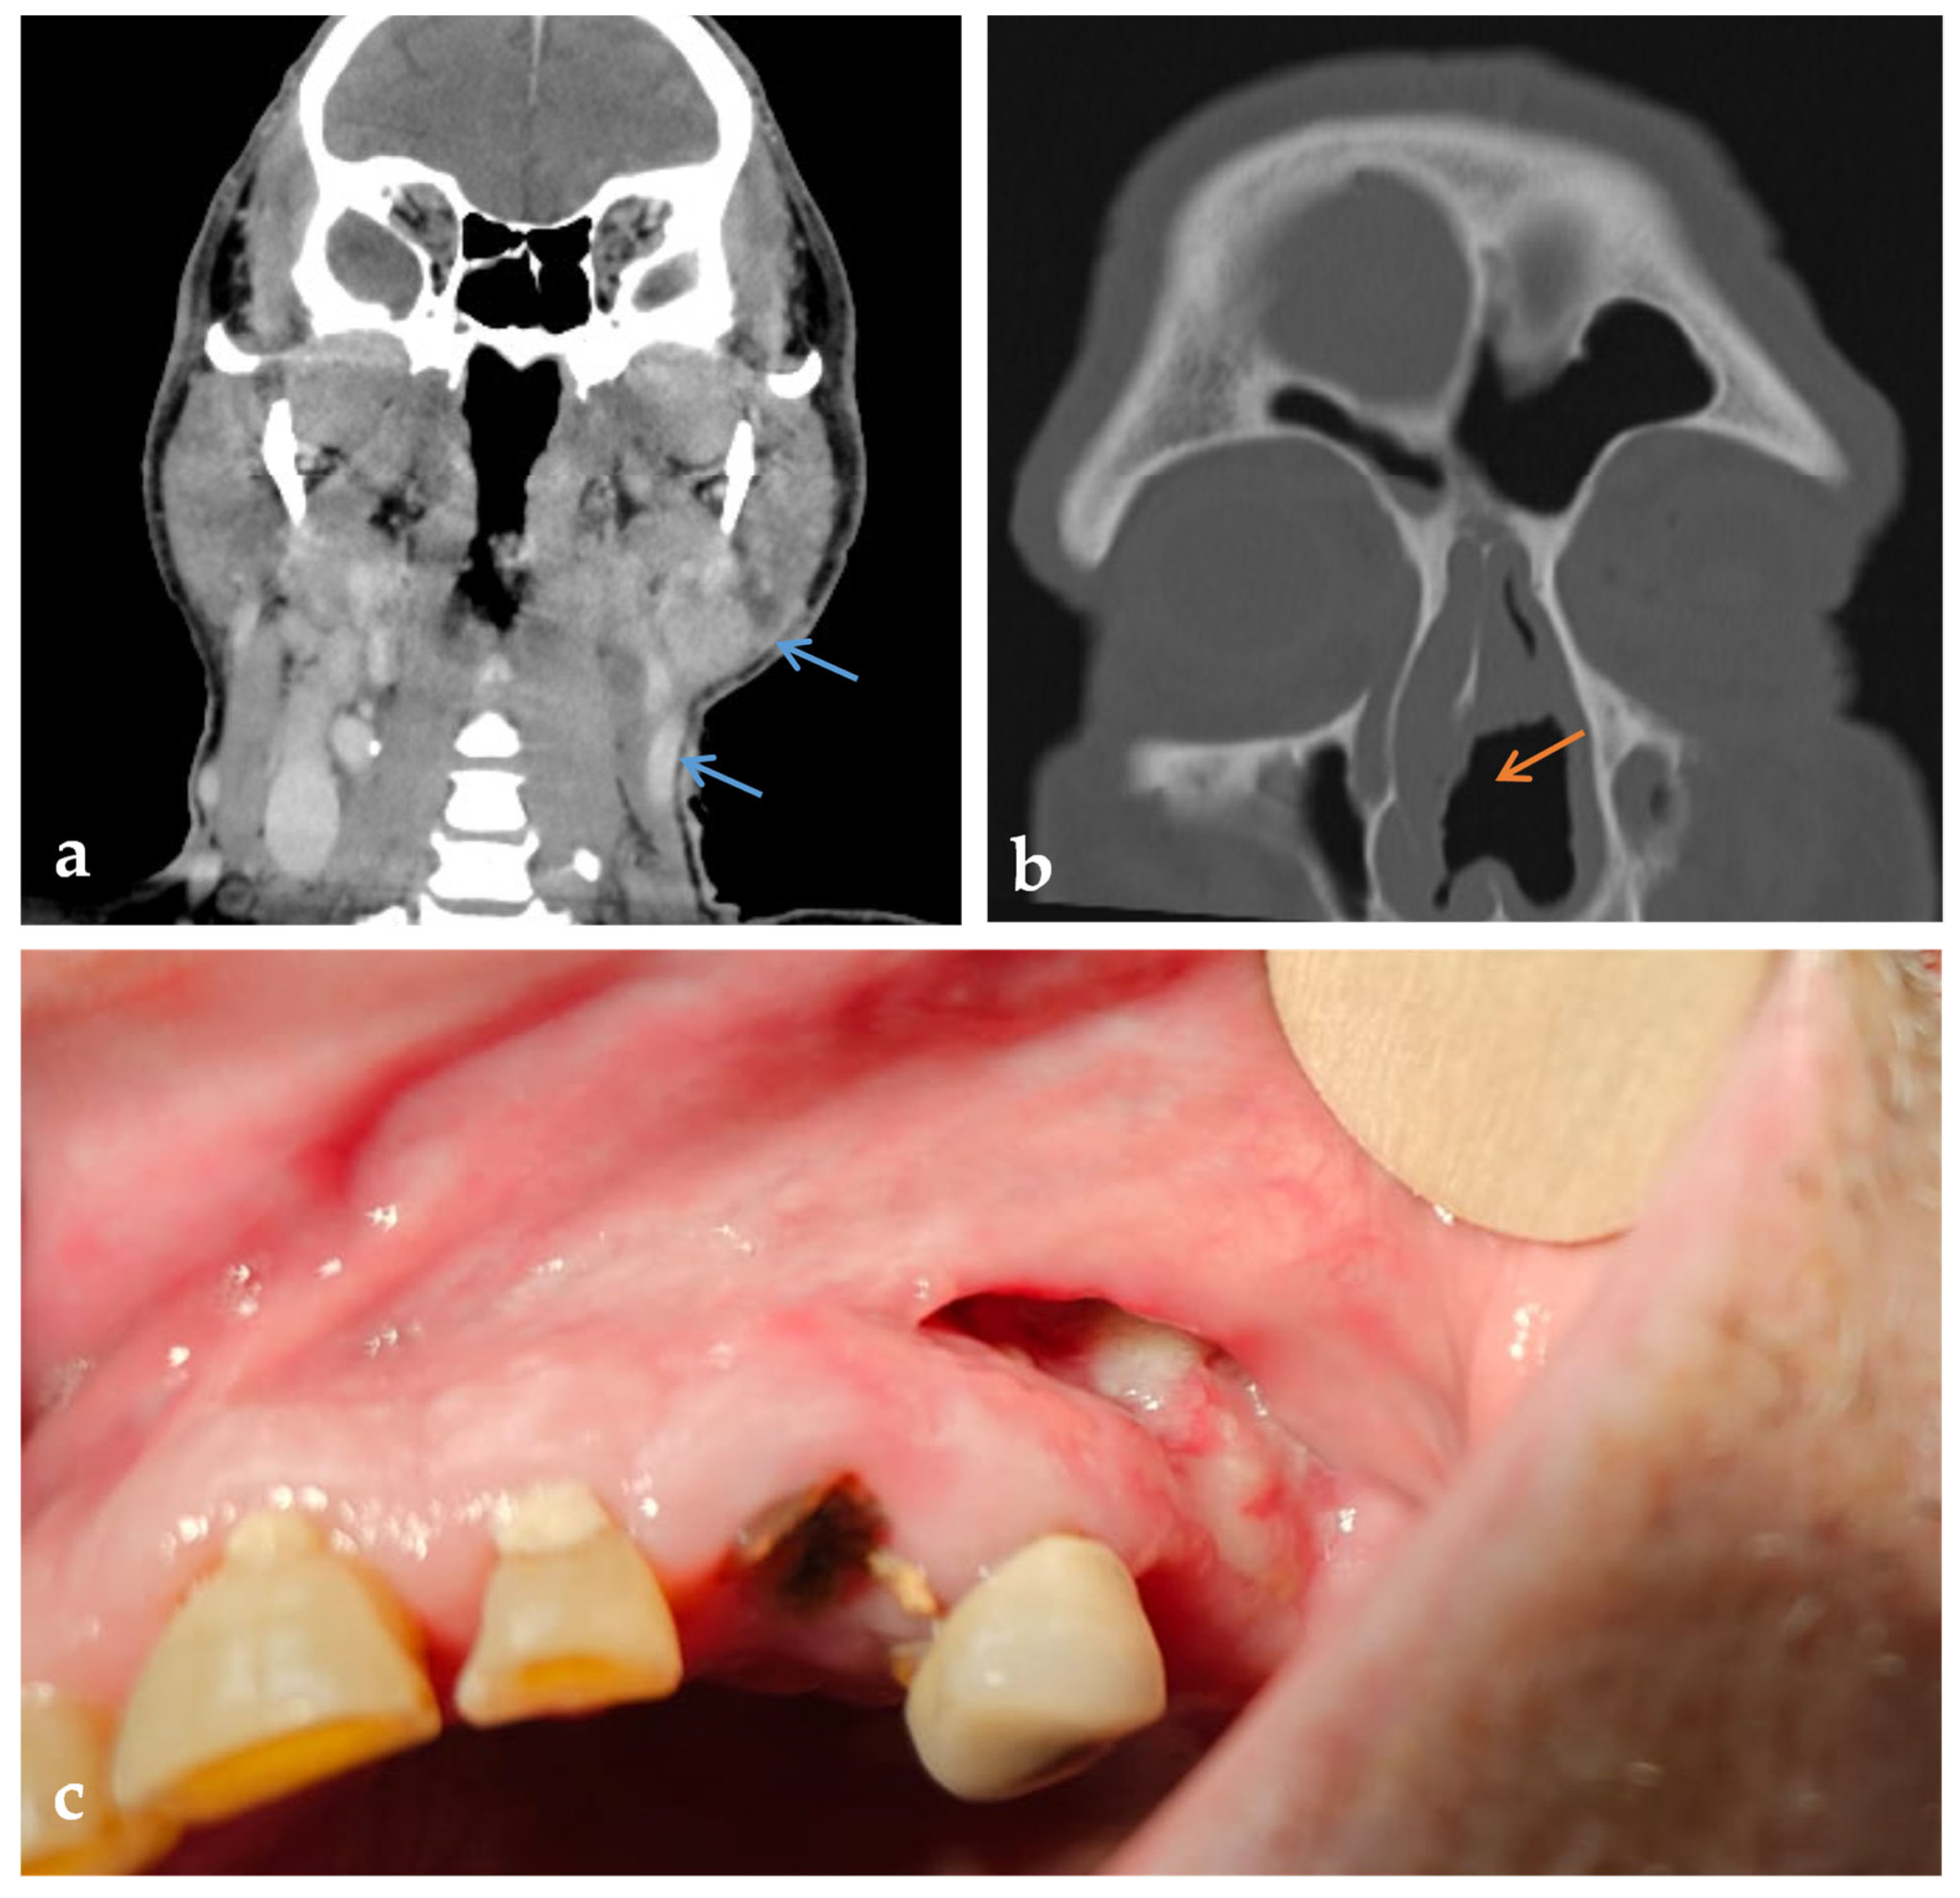

2. Case Presentation